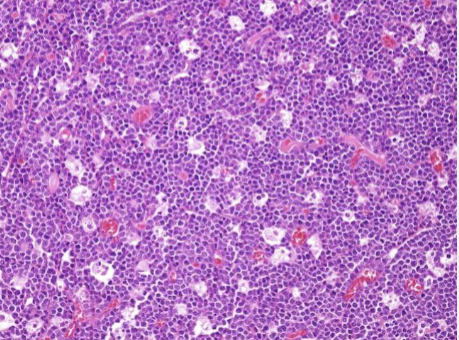

Burkitt lymphoma

Starry Sky

Highly aggressive B-cell neoplasm characterized by the overexpression of the Myc gene on Chromosome 8

Translocation is the IgH heavy chain locus t(8;14)

Starry Sky appearance due to evenly interspersed macrophages with apoptotic debris in cytoplasm

Intermediate to small cells with noncleaved nuclei, coarse chromatin, small multiple nucleoli & very high mitotic index

African (endemic) Burkitt:

Very strong association with EBV

Extranodal, facial; tends to involve mandible & abdominal visceral organs

Burkitt lymphoma in HIV:

Intermediate association with EBV

Extranodal sites (GI, Bone marrow)

Sporadic Burkitt lymphoma in the US:

Weak association with EBV

Usually presents as mass of ileocecum/peritoneum

Both endemic & sporadic tends to occur in children or young adults